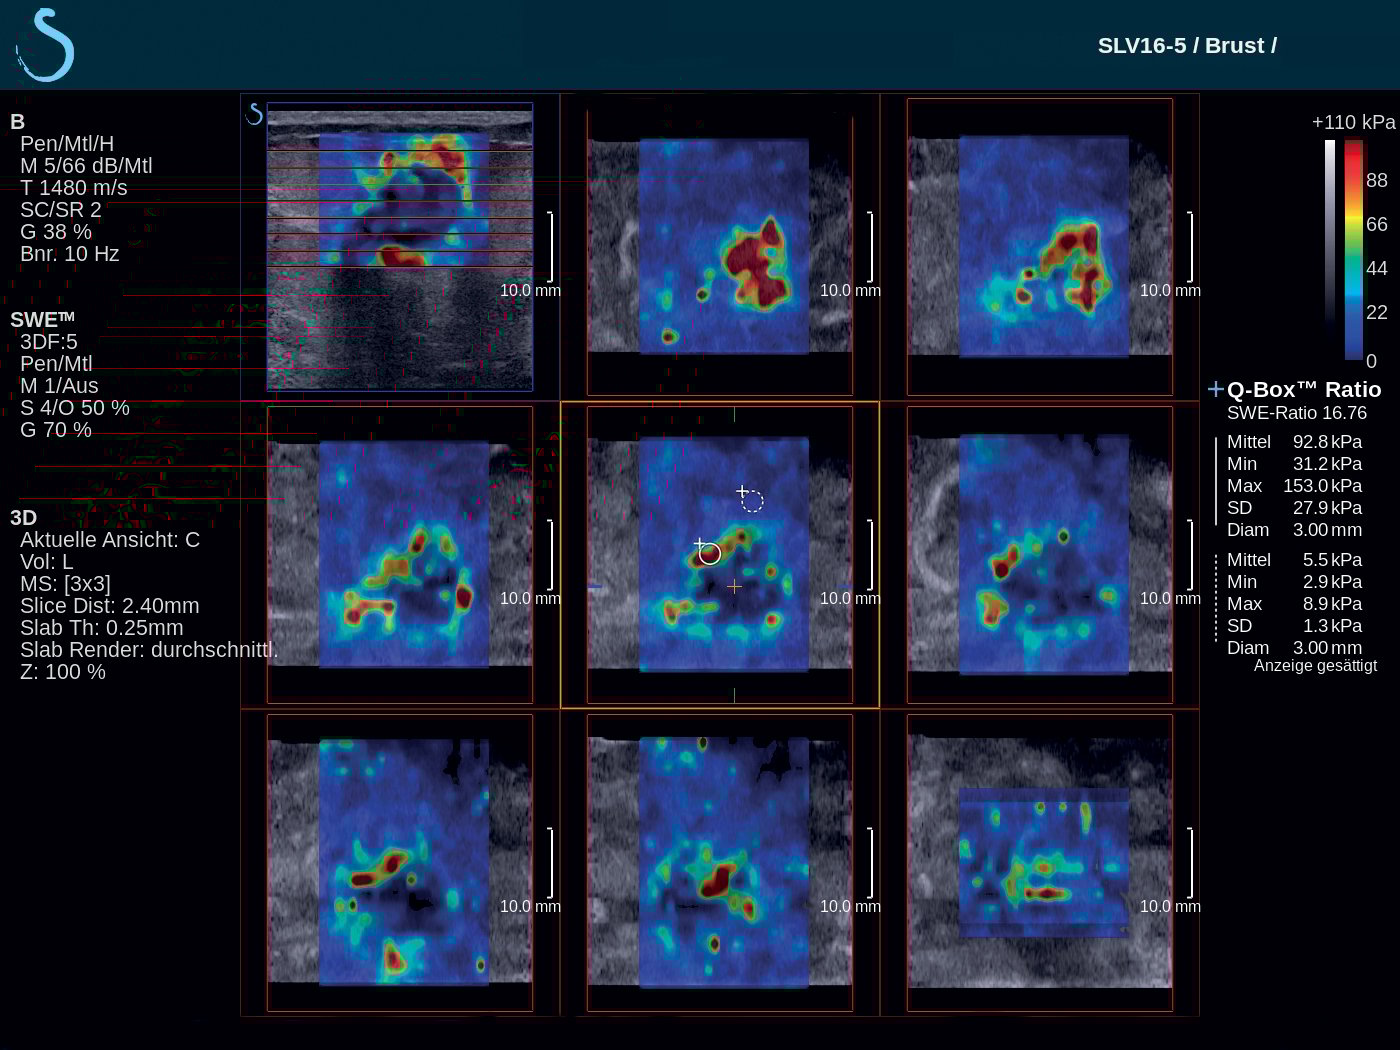

French-based ultrasound company Supersonic Imagine introduced the Aixplorer Mach 30 with Shear Wave Elastography (SWE) Plus functionality, which it highlighted at the 2019 Society of Breast Imaging/American College of Radiology (SBI/ACR) symposium in April. Shear wave elastography is a technique that measures the stiffness of tissue with ultrasound waves; this can provide important diagnostic information about the organ or structure in question. In breast imaging, the technique can help distinguish whether a mammary lesion is benign or malignant. SWE Plus on the Aixplorer Mach 30, which SuperSonic Imagine bills as the next generation of the technology, offers greater performance of real-time, reliable, quantitative and reproducible evaluation of tissue stiffness and visualization. It offers greater diagnostic precision, which considerably reduces the number of false positives and unnecessary biopsies.